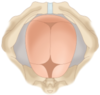

¿cuál es el punto de referencia óseo o toconómico para determinar la variedad de posición fetal en presentación cefálica?

¿cuál es la variedad de posición fetal cefálica en obstetricia en donde la fontanela posterior esta en estrecha relación con la sínfisis púbica a 0º?

Posición occipitopúbica

¿Cuales son las 8 variedades de posición que puede tener un bebe cuando el punto toconómico es el occipucio?

- Occipitopúbica

- Occipitoanterior izquierda

- Occipitoanterior derecha

- Occipito-transversa izquierda

- Occipito-transversa derecha

- Occipitoposterior izquierda

- Occipitoposterior derecha

- Occipitosacra

¿Cual es la única variedad de posición cefálica que permite el nacimiento de un feto?

Occipitopúbica